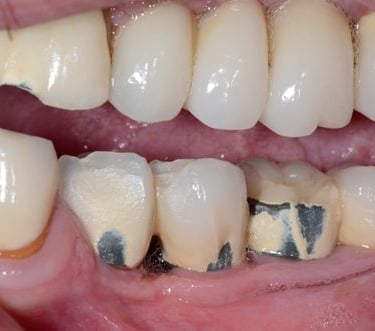

Pérdida de múltiples dientes

La pérdida de múltiples dientes es la ausencia de varios dientes que puede ser resultado de caries, enfermedades periodontales o traumatismos.

Los pacientes notan varios espacios vacíos en su boca, lo que afecta su capacidad para masticar y hablar adecuadamente.

El tratamiento incluye la colocación de varios implantes dentales para restaurar la función y la estética.